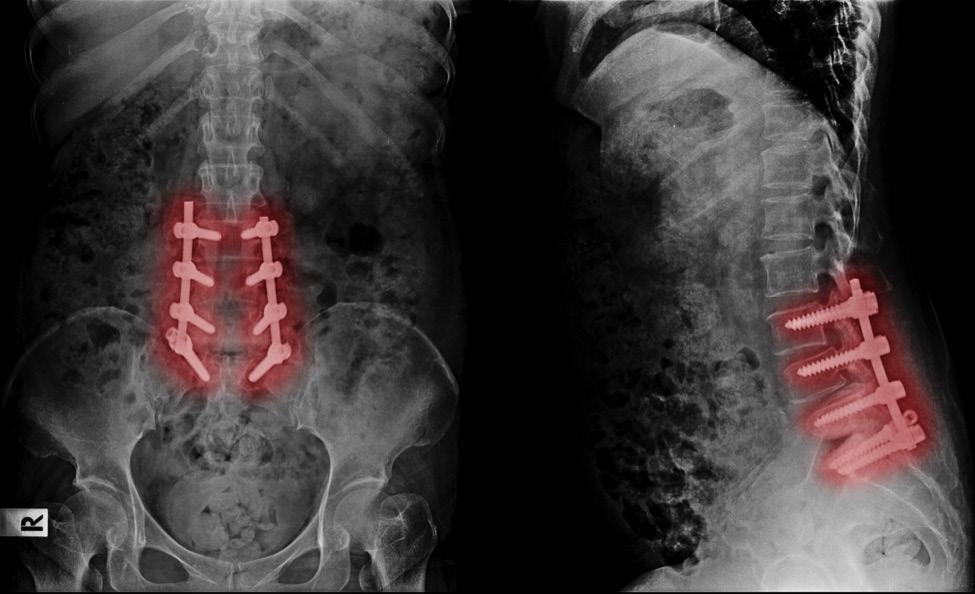

A: I do and it does. I completely changed the way I play. Being a taller guy, I was usually in the post. Sometime in residency, I hurt my back doing that and ended up getting back surgery. After that, I changed the way I play. I don’t really play the post much anymore.